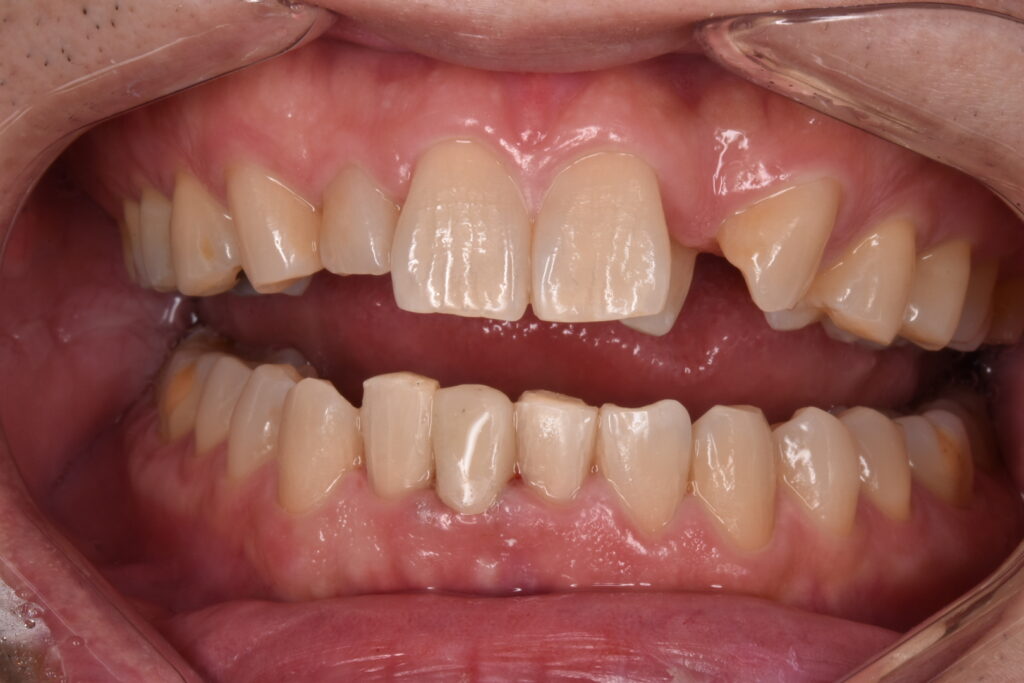

50代男性 下の前歯が東京の歯科で一年ほど前に作られた差し歯で、今回はそれが取れてしまったとご相談いただきました。検査の結果、歯が土台ごと折れていました。折れている場所が歯茎の中の方で折れていて、歯槽骨ギリギリの場所です。

歯が破折していることに大変ショック受けられていました。丁寧にお話を伺い費用をかけてでもご自身の歯をもう一度使えるなら自分の歯でできるだけ過ごしたいと仰ってくださいました。

歯が折れてしまっている現状では、このままセラミックをやりかえても予後が悪く長持ちしない点をお伝えしました。そこでご自身の歯を上に引っ張り出して骨からの距離を出してからセラミックで修復する意図的挺出(いとてきていしゅつ)をご提案させて頂きました。